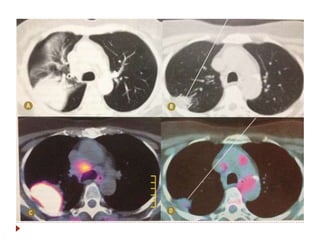

 Critérios de resposta

 Comparação dos exames pós-tratamento com o exame

baseline.

 Lesões-alvo

 Resposta parcial

 Redução de pelo menos 30% da soma dos diâmetros das lesões-alvo.

 Progressão de doença

 Aumento de pelo menos 20% da soma dos diâmetros das lesões-alvo.

 Doença estável

 Sem mudança suficiente para se encaixar em outra classificação.

RECIST  Critérios deresposta  Comparação dos exames pós-tratamento com o exame baseline.  Lesões-alvo  Resposta completa  Desaparecimento de todas as lesões.  LND patologicos devem ter reduzido a menos de 10mm  Lesões residuais x fibrocicatricial  PET CT/ biópsia.  Resposta parcial  Redução de pelo menos 30% da soma dos diâmetros das lesões-alvo.  Progressão de doença  Aumento de pelo menos 20% da soma dos diâmetros das lesões-alvo.  Doença estável  Sem mudança suficiente para se encaixar em outra classificação.